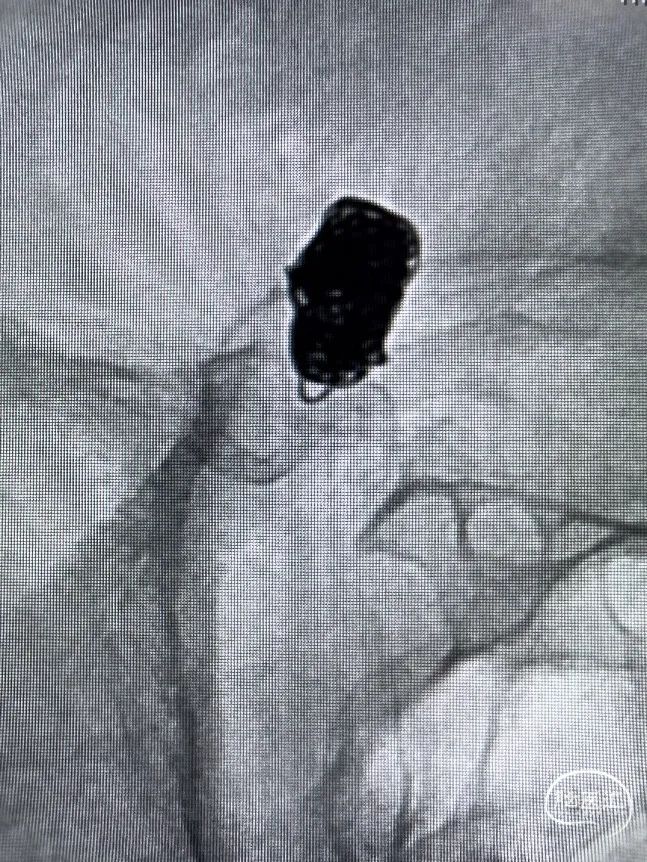

术中操作-预置支架导管+填圈:

预置支架导管

置入弹簧圈微导管

置入弹簧圈

填圈后通过微导管并释放支架

导丝通过&支架导管到位

释放支架:

支架到位

头端打开

中间打开

近端打开,后予以支架导管通过支架将其充分打开。

术后即刻复查:远端血管通畅、支架打开良好。

术后正位复查